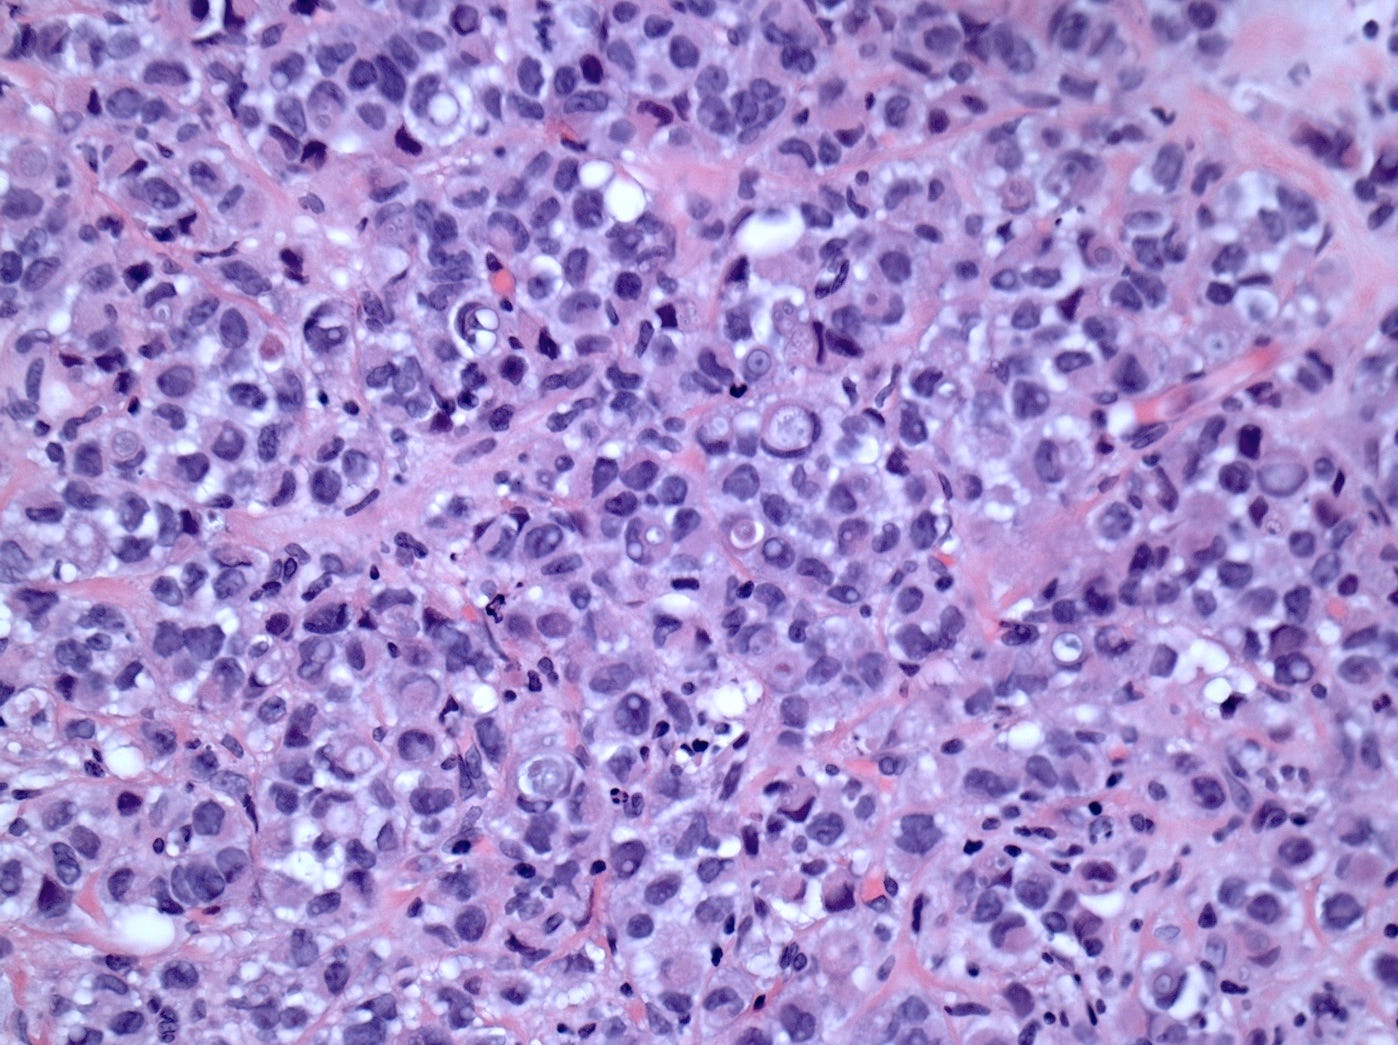

Lobular carcinoma is a common type of invasive breast carcinoma (10% of cases). It is characterized by the loss of cellular adhesion with dyscohesive tumor cells arranged in single file or as individual single cells. The cells show a loss of 16q (the CDH1 gene located at 16q22.1 encodes E-cadherin, essential in forming the adherens junction responsible for cell adhesion). Loss of E-cadherin protein expression by immunohistochemistry is helpful but not required for diagnosis.

Classic lobular carcinoma - microscopic images

The premalignant precursors of classic lobular carcinoma are classic lobular carcinoma in situ (classic LCIS), its variants florid LCIS and pleomorphic LCIS, and atypical lobular hyperplasia (ALH).